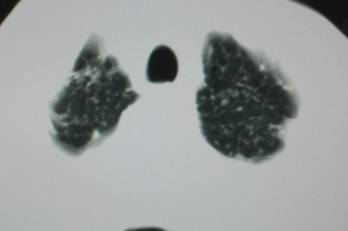

以下是引用卜一在2008-6-3 19:33:00的发言:[br]双肺结节,以双上肺分布为多,期间搀杂片状致密影及索条致密影。考虑:继发性肺结核伴血型播散可能性大。不除外肺泡ca的可能!另:椎体退变!

以下是引用医影拾贝在2008-6-3 18:48:00的发言:[br]双上肺弥漫性小结节影,纵隔窗内钙化淋巴结影,考虑血播性tb可能性较大,不除外肺ca可能

以下是引用panyishengct在2008-6-3 21:09:00的发言:[br]双上肺弥漫性小结节影,纵隔窗内钙化淋巴结影,考虑矽肺或/和tb可能性较大,不除外肺ca可能。腰椎考虑退变。 [br][br]